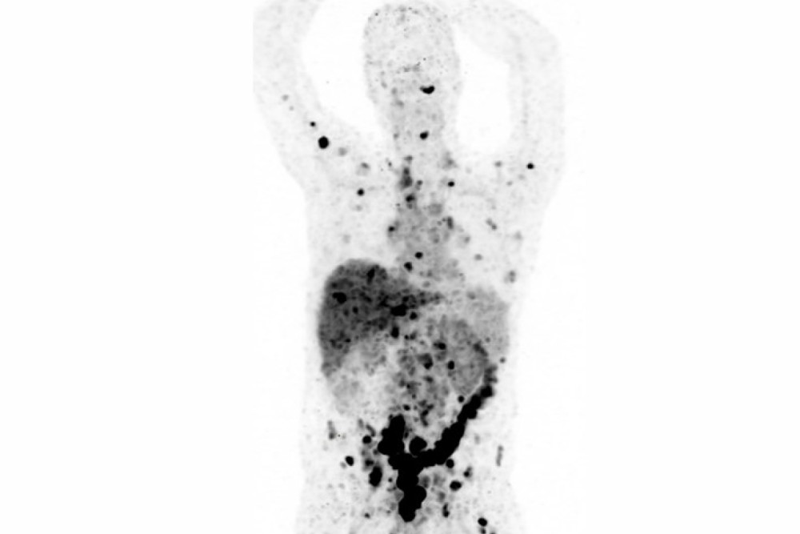

图注:转移性癌症的PET扫描图像。DLL3靶向技术可以检测到一些传统影像手段可能会遗漏的癌症,例如这种已在全身扩散的神经内分泌型前列腺癌(NEPC)(图中黑点)(图片来自MSK官网)